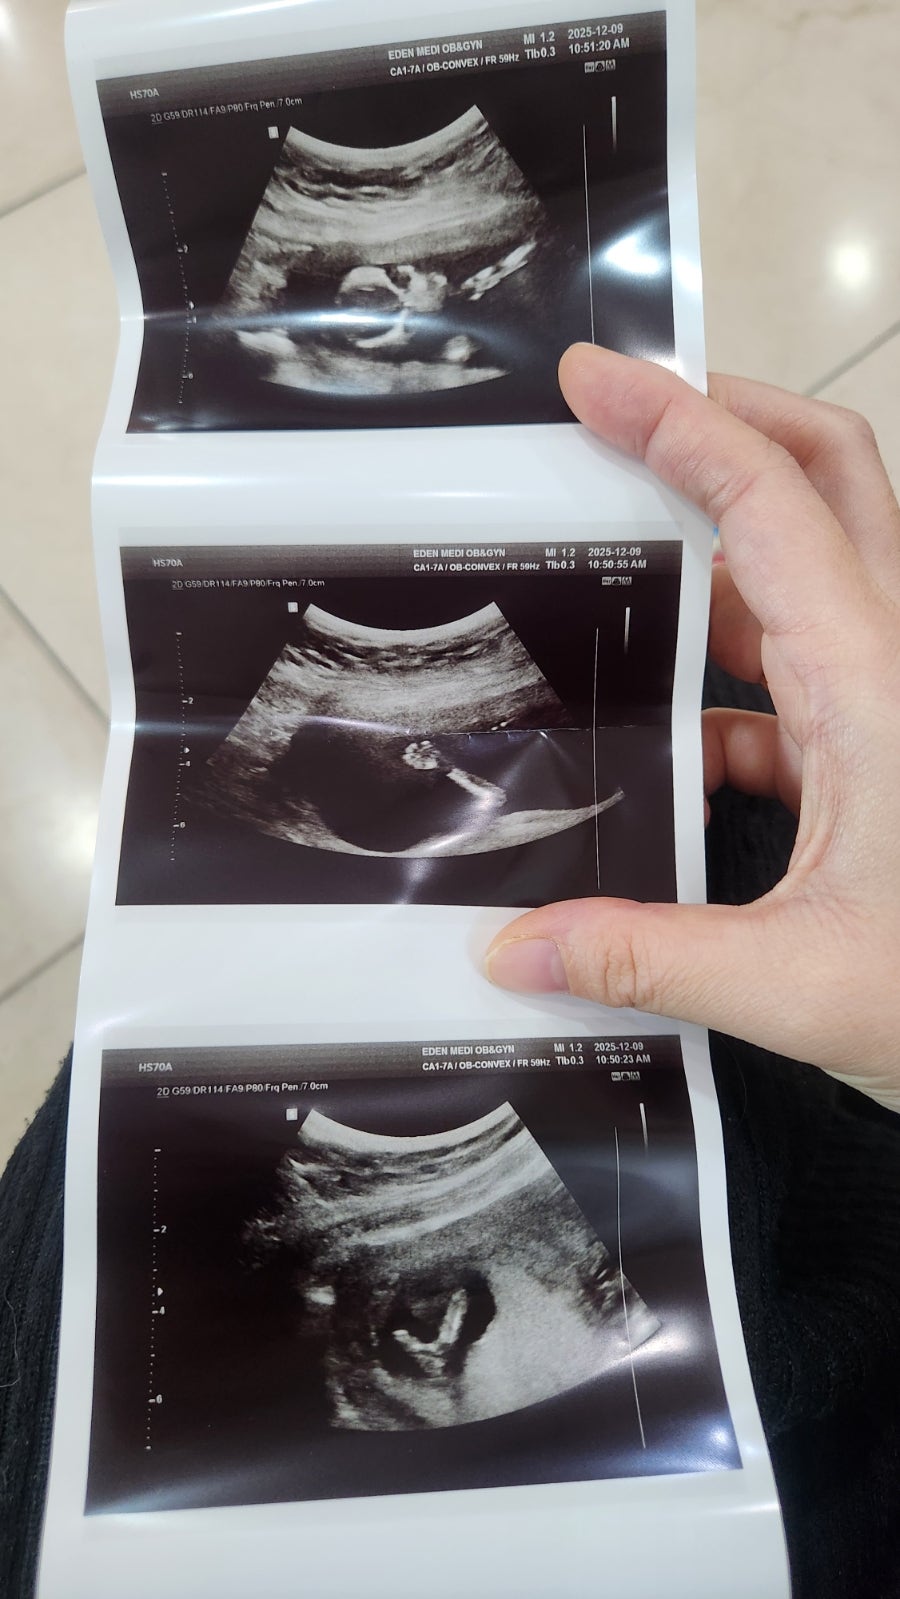

엊그제 산부인과 진료날이라서 다녀왓어요! 저는 첫째 아들 20개월아기 키우고있습니당 둘째 계획하자마자 임신이 되어서 벌써 14주차네요!! 첫째가 아들이라서 둘째는 딸을 조금 바랬지만 상관없어용 ㅎㅎㅎ 형제~ 도 좋고 아둘맘이면 어때요 다 소중하고 이쁘고 사랑스러운 내새끼인걸요 ㅎㅎㅎ 원장님께서 뭔가 볼록 나온거같다 왕자님일거같지만 2주뒤에 다시 보자구햇어용~ 확실하지않다구 하셔서... 다리를 너무 꼬고 있어서 잘 보여주지 않았던 우리 둘째 뽀물이 ㅋㅋㅋㅋㅋㅋ 혹시 14주정도에 남아인거같습니다 햇는데 여아로 성별 반전 ~~ 나온적이 있나해서 올려보아요 ㅎㅎ 여아에서 남아로 성별반전이 많은데 ~ 남아에서 여아반전은 생각보다 없네용 ㅎㅎ